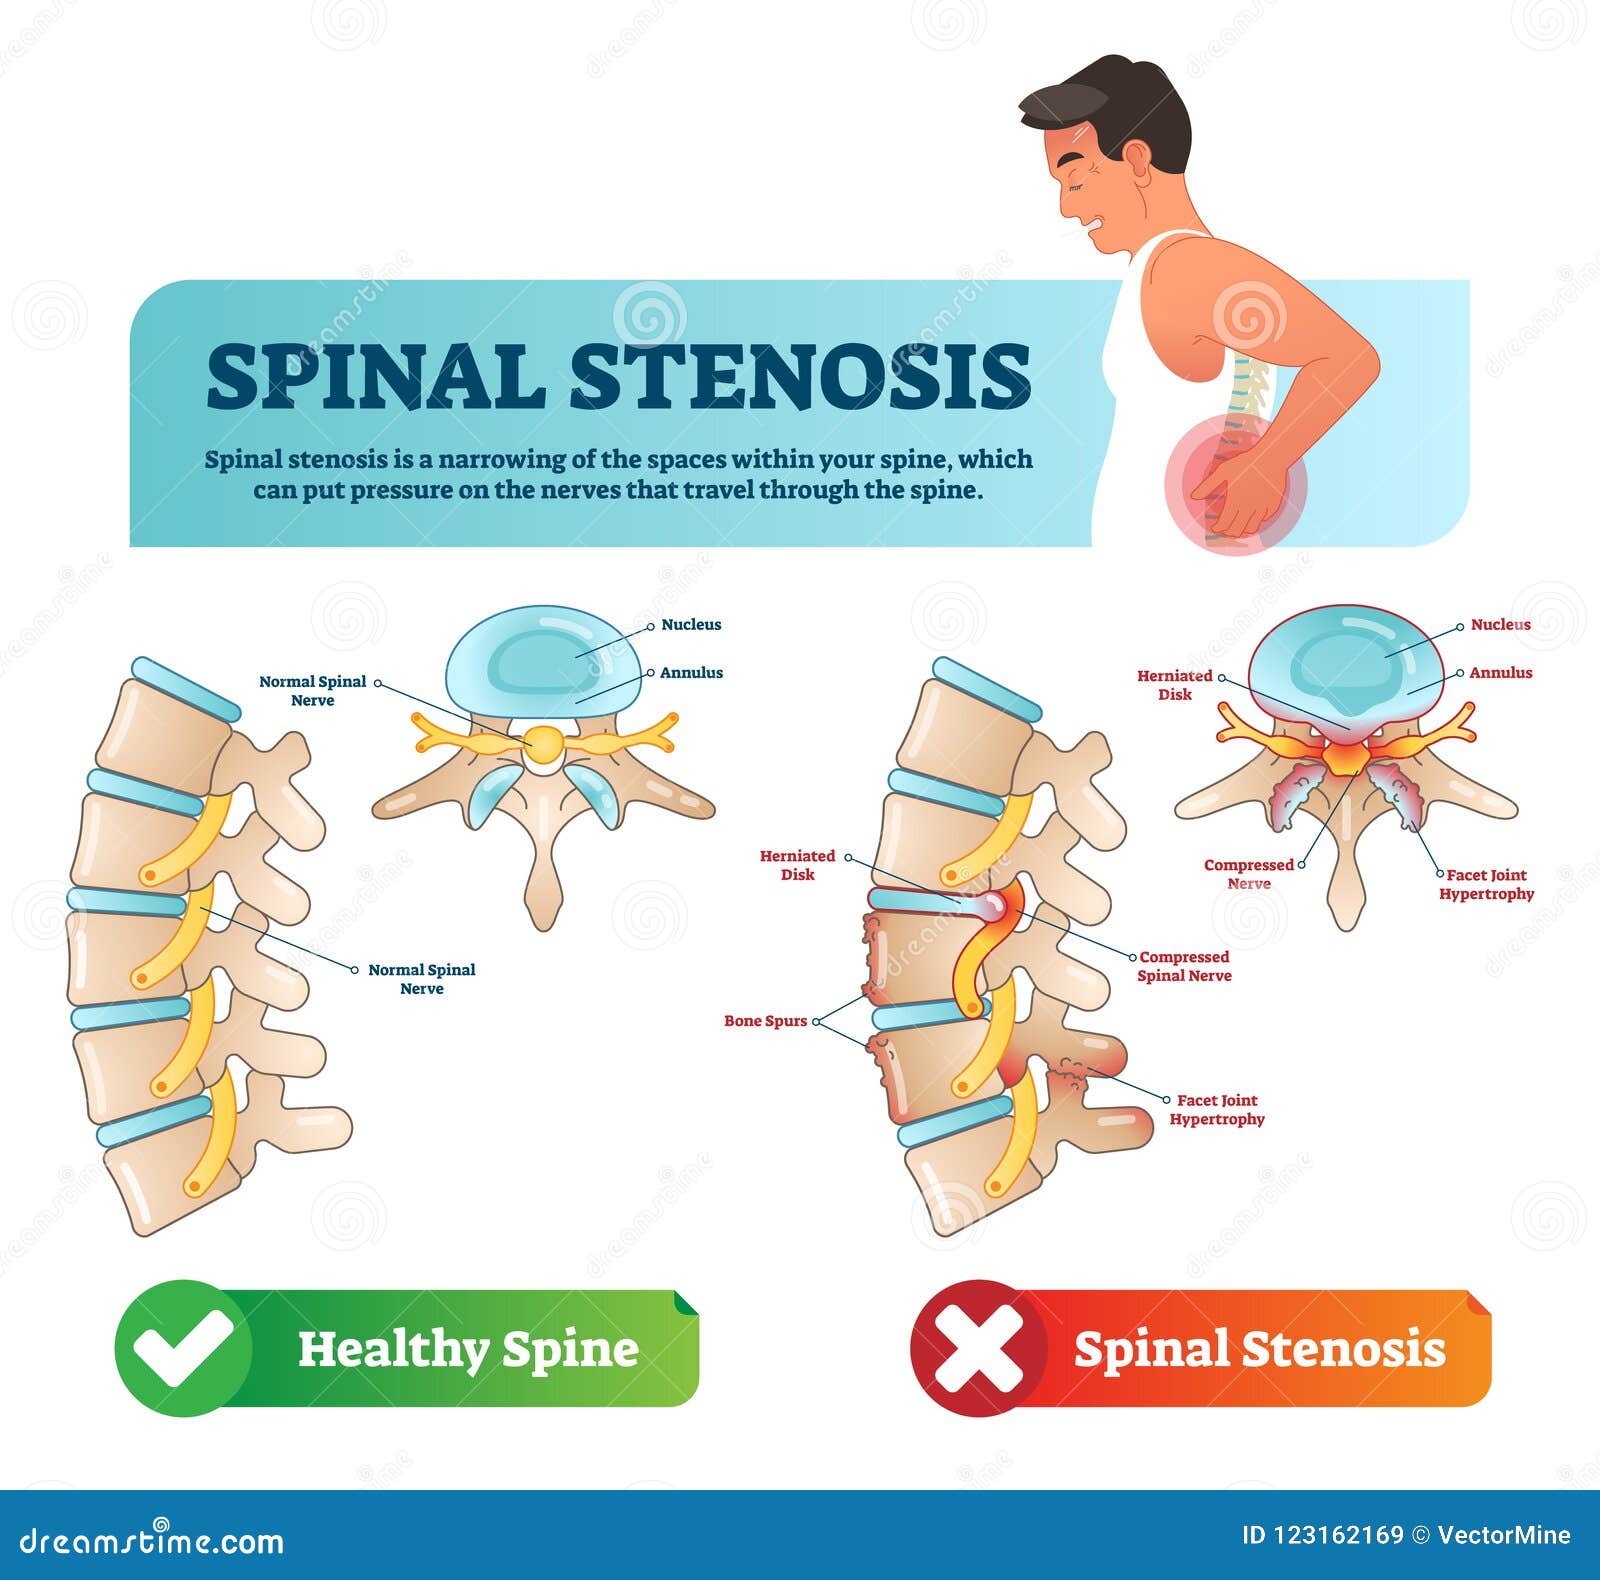

Pictures: neck bone spurs | Spinal Stenosis — Stock Photo © lightsource …

Spinal Stenosis Cartoon Vector | CartoonDealer.com #34680607

Spinal Stenosis Treatment | Bone Spur Treatment In Houston By Dr. West